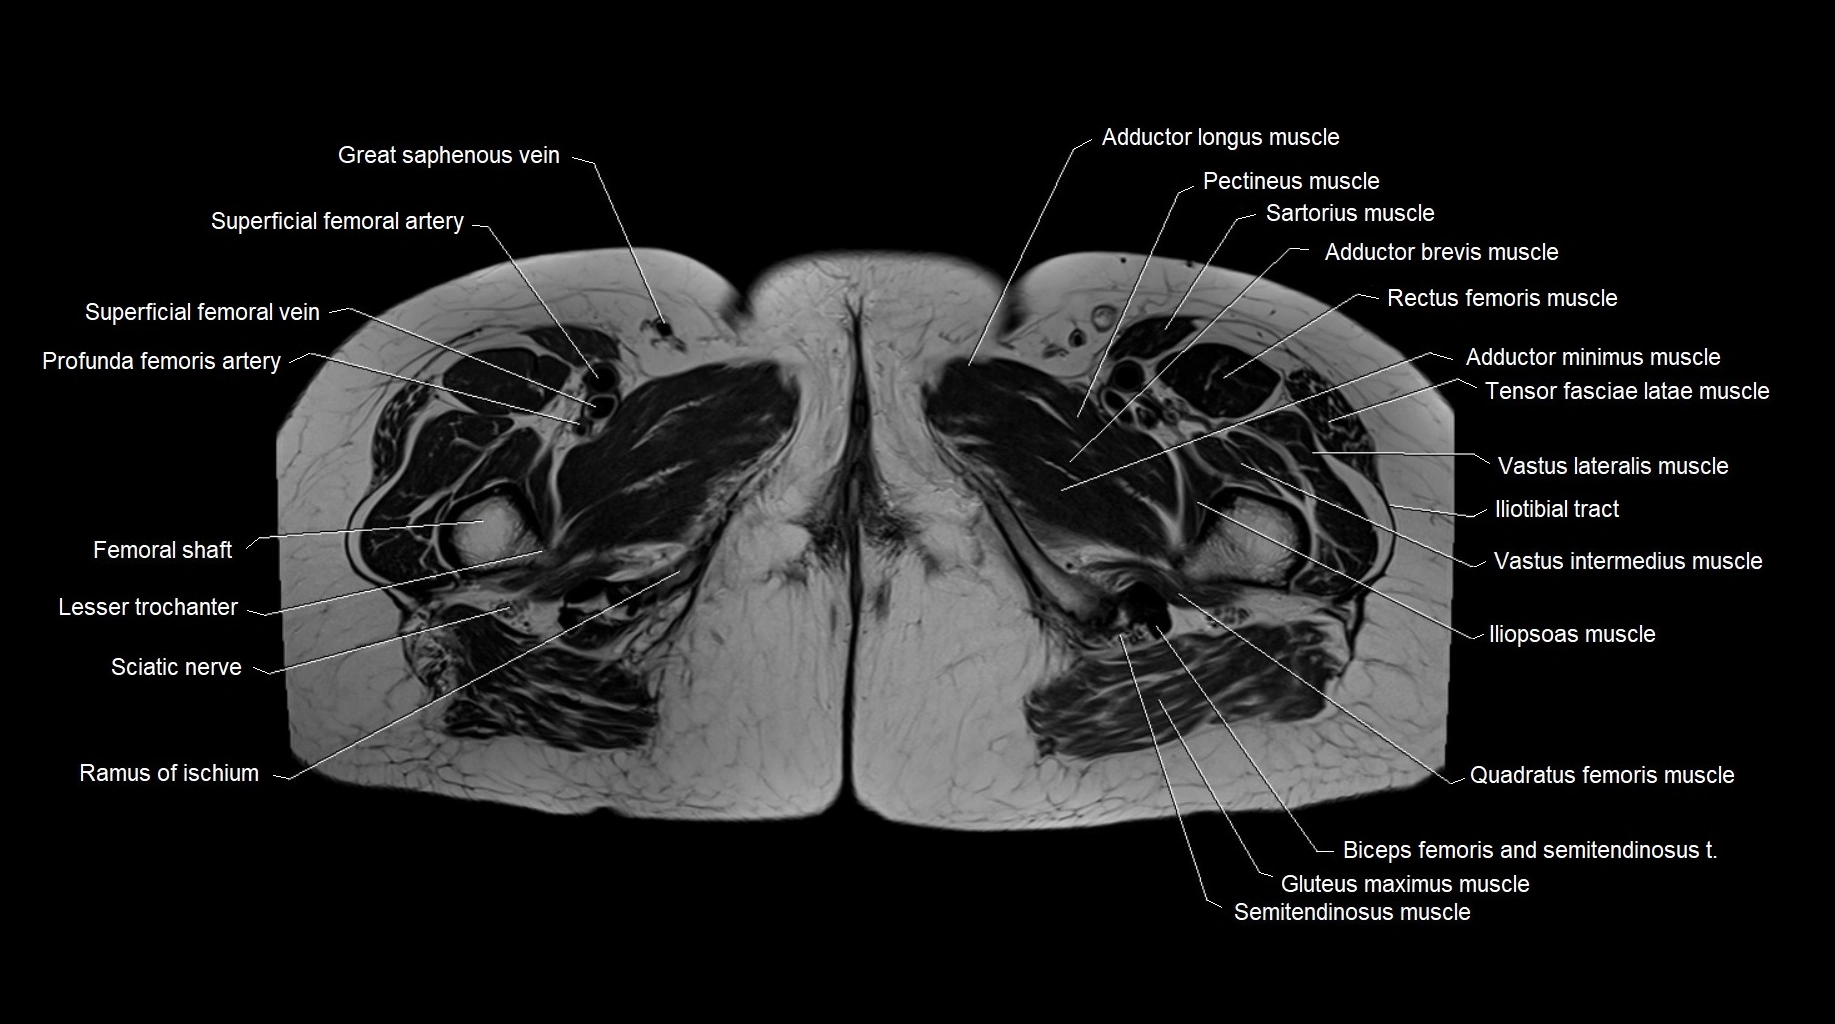

- Adductor brevis muscle

- Adductor longus muscle

- Adductor minimus muscle

- Deep femoral artery (profunda femoris)

- Femoral shaft

- Iliopsoas muscle

- Iliotibial tract

- Lesser trochanter

- Pectineus muscle

- Quadratus femoris muscle

- Ramus of ischium

- Rectus femoris muscle

- Sciatic nerve

- Superficial femoral artery

- Vastus intermedius muscle

- Vastus lateralis muscle

- great saphenous vein